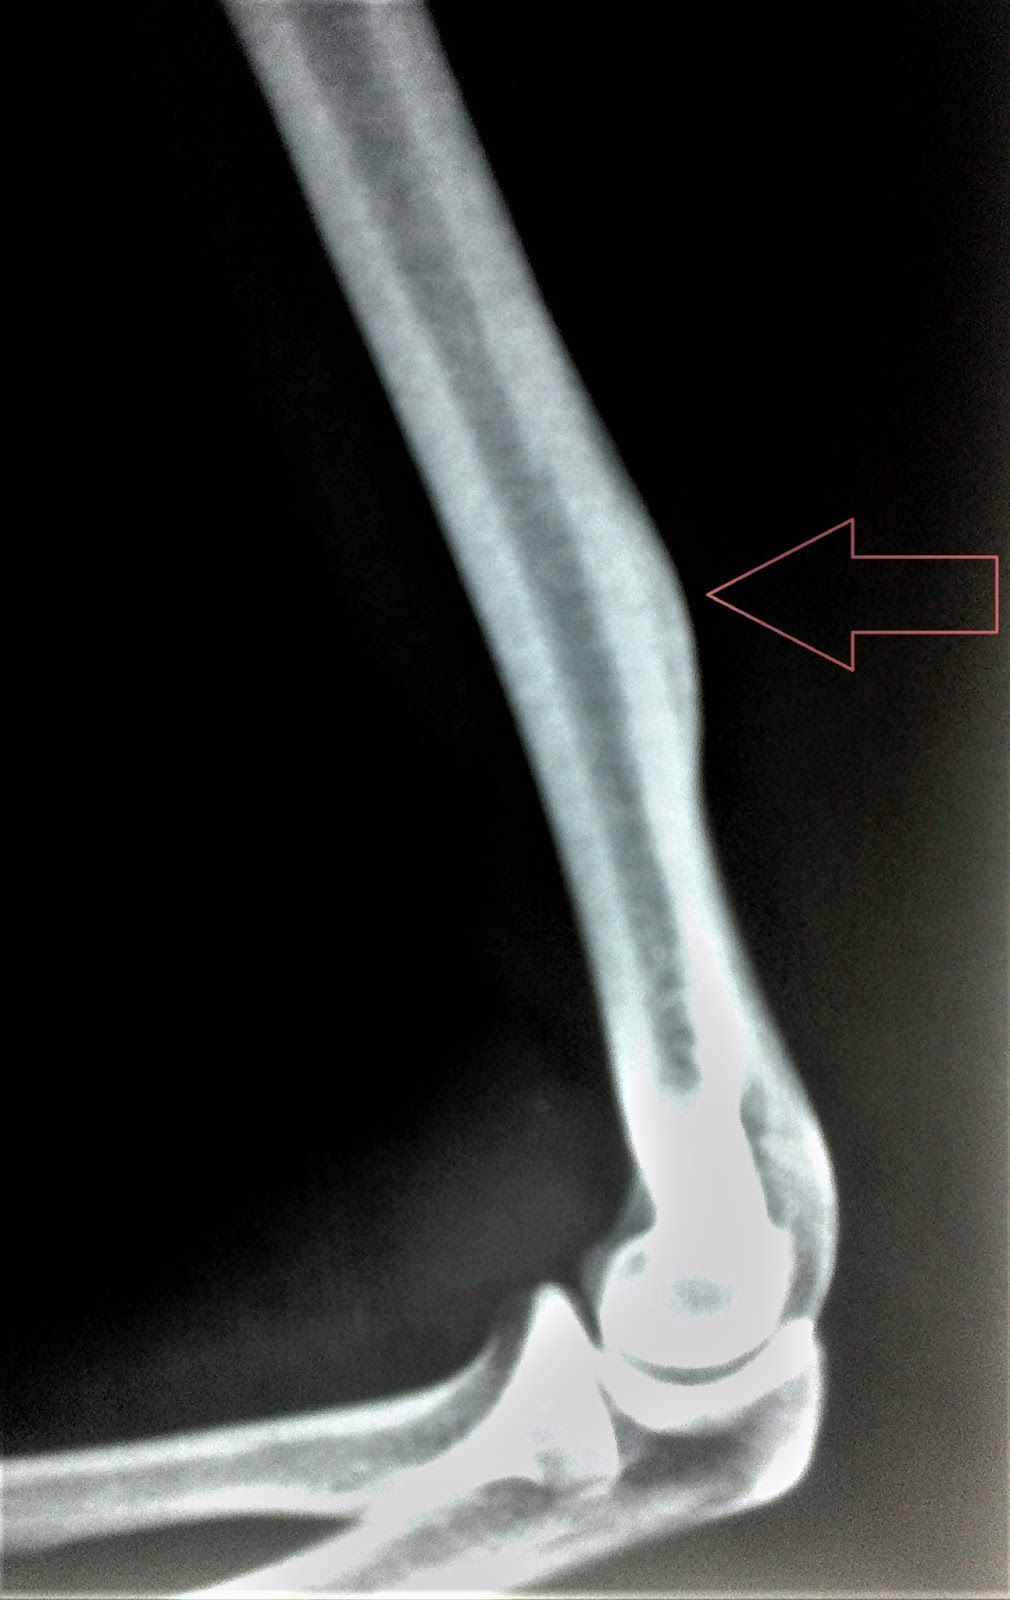

Osteoid osteoma has characteristic night pain that gets dramatically relieved on taking NSAIDS. The radiograph also depicts localised cortical growth, however, CT scan in thin section around the lesion is better I investigation.

The percutaneous radio frequency ablation is widely considered as treatment of choice in cases if osteoid osteoma. That's why this should be the lesion.

Apart from it , one interesting g clue in the question is night pain. Pain in the night that is drastically improves on taking NSAIDS is characteristic feature of osteoid osteoma.